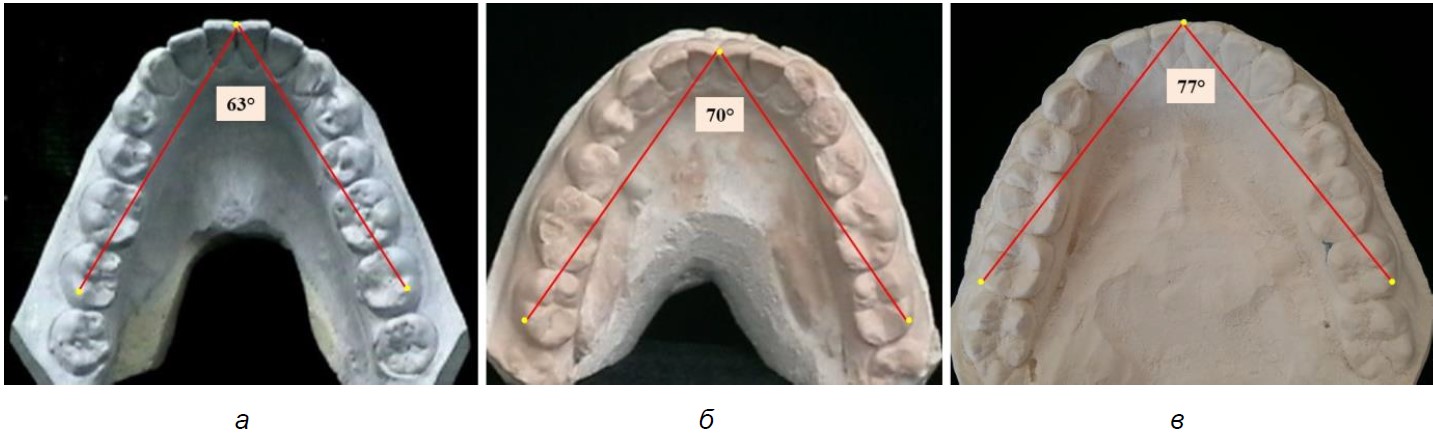

Анализ угловых параметров верхней челюсти на моделях челюстей, относящихся к III группе (протрузионный тип), проведенный методом математического расчета, показал, что отношение глубины зубной дуги к диагонали составило (0,83 ± 0,01) мм и соответствовало синусу резцово-молярного угла, величина которого варьировала от 55 до 57°. На долю центрального (резцового) угла верхней челюсти при протрузии резцов приходилась величина менее 68°.

Варианты резцового (центрального) угла верхней челюсти при различных трузионных типах зубных дуг представлены на рис. 3.

Рис. 3. Резцово-молярный угол зубных дуг верхней челюсти протрузионного (а), мезотрузионного (б) и ретрузионного (в) типов

Анализ угловых параметров нижней челюсти на моделях челюстей, относящихся к III группе (протрузионный тип), показал, что отношение глубины зубной дуги к диагонали составило 0,83 ± 0,01 и соответствовало синусу резцово-молярного угла, величина которого варьировала от 55 до 57°. На долю центрального (резцового) угла верхней челюсти при протрузии резцов приходилась величина менее 68°. Варианты резцового (центрального) угла нижней челюсти при различных трузионных типах зубных дуг представлены на рис. 5.

Рис. 5. Резцово-молярный угол зубных дуг нижней челюсти протрузионного (а), мезотрузионного (б) и ретрузионного (в) типов